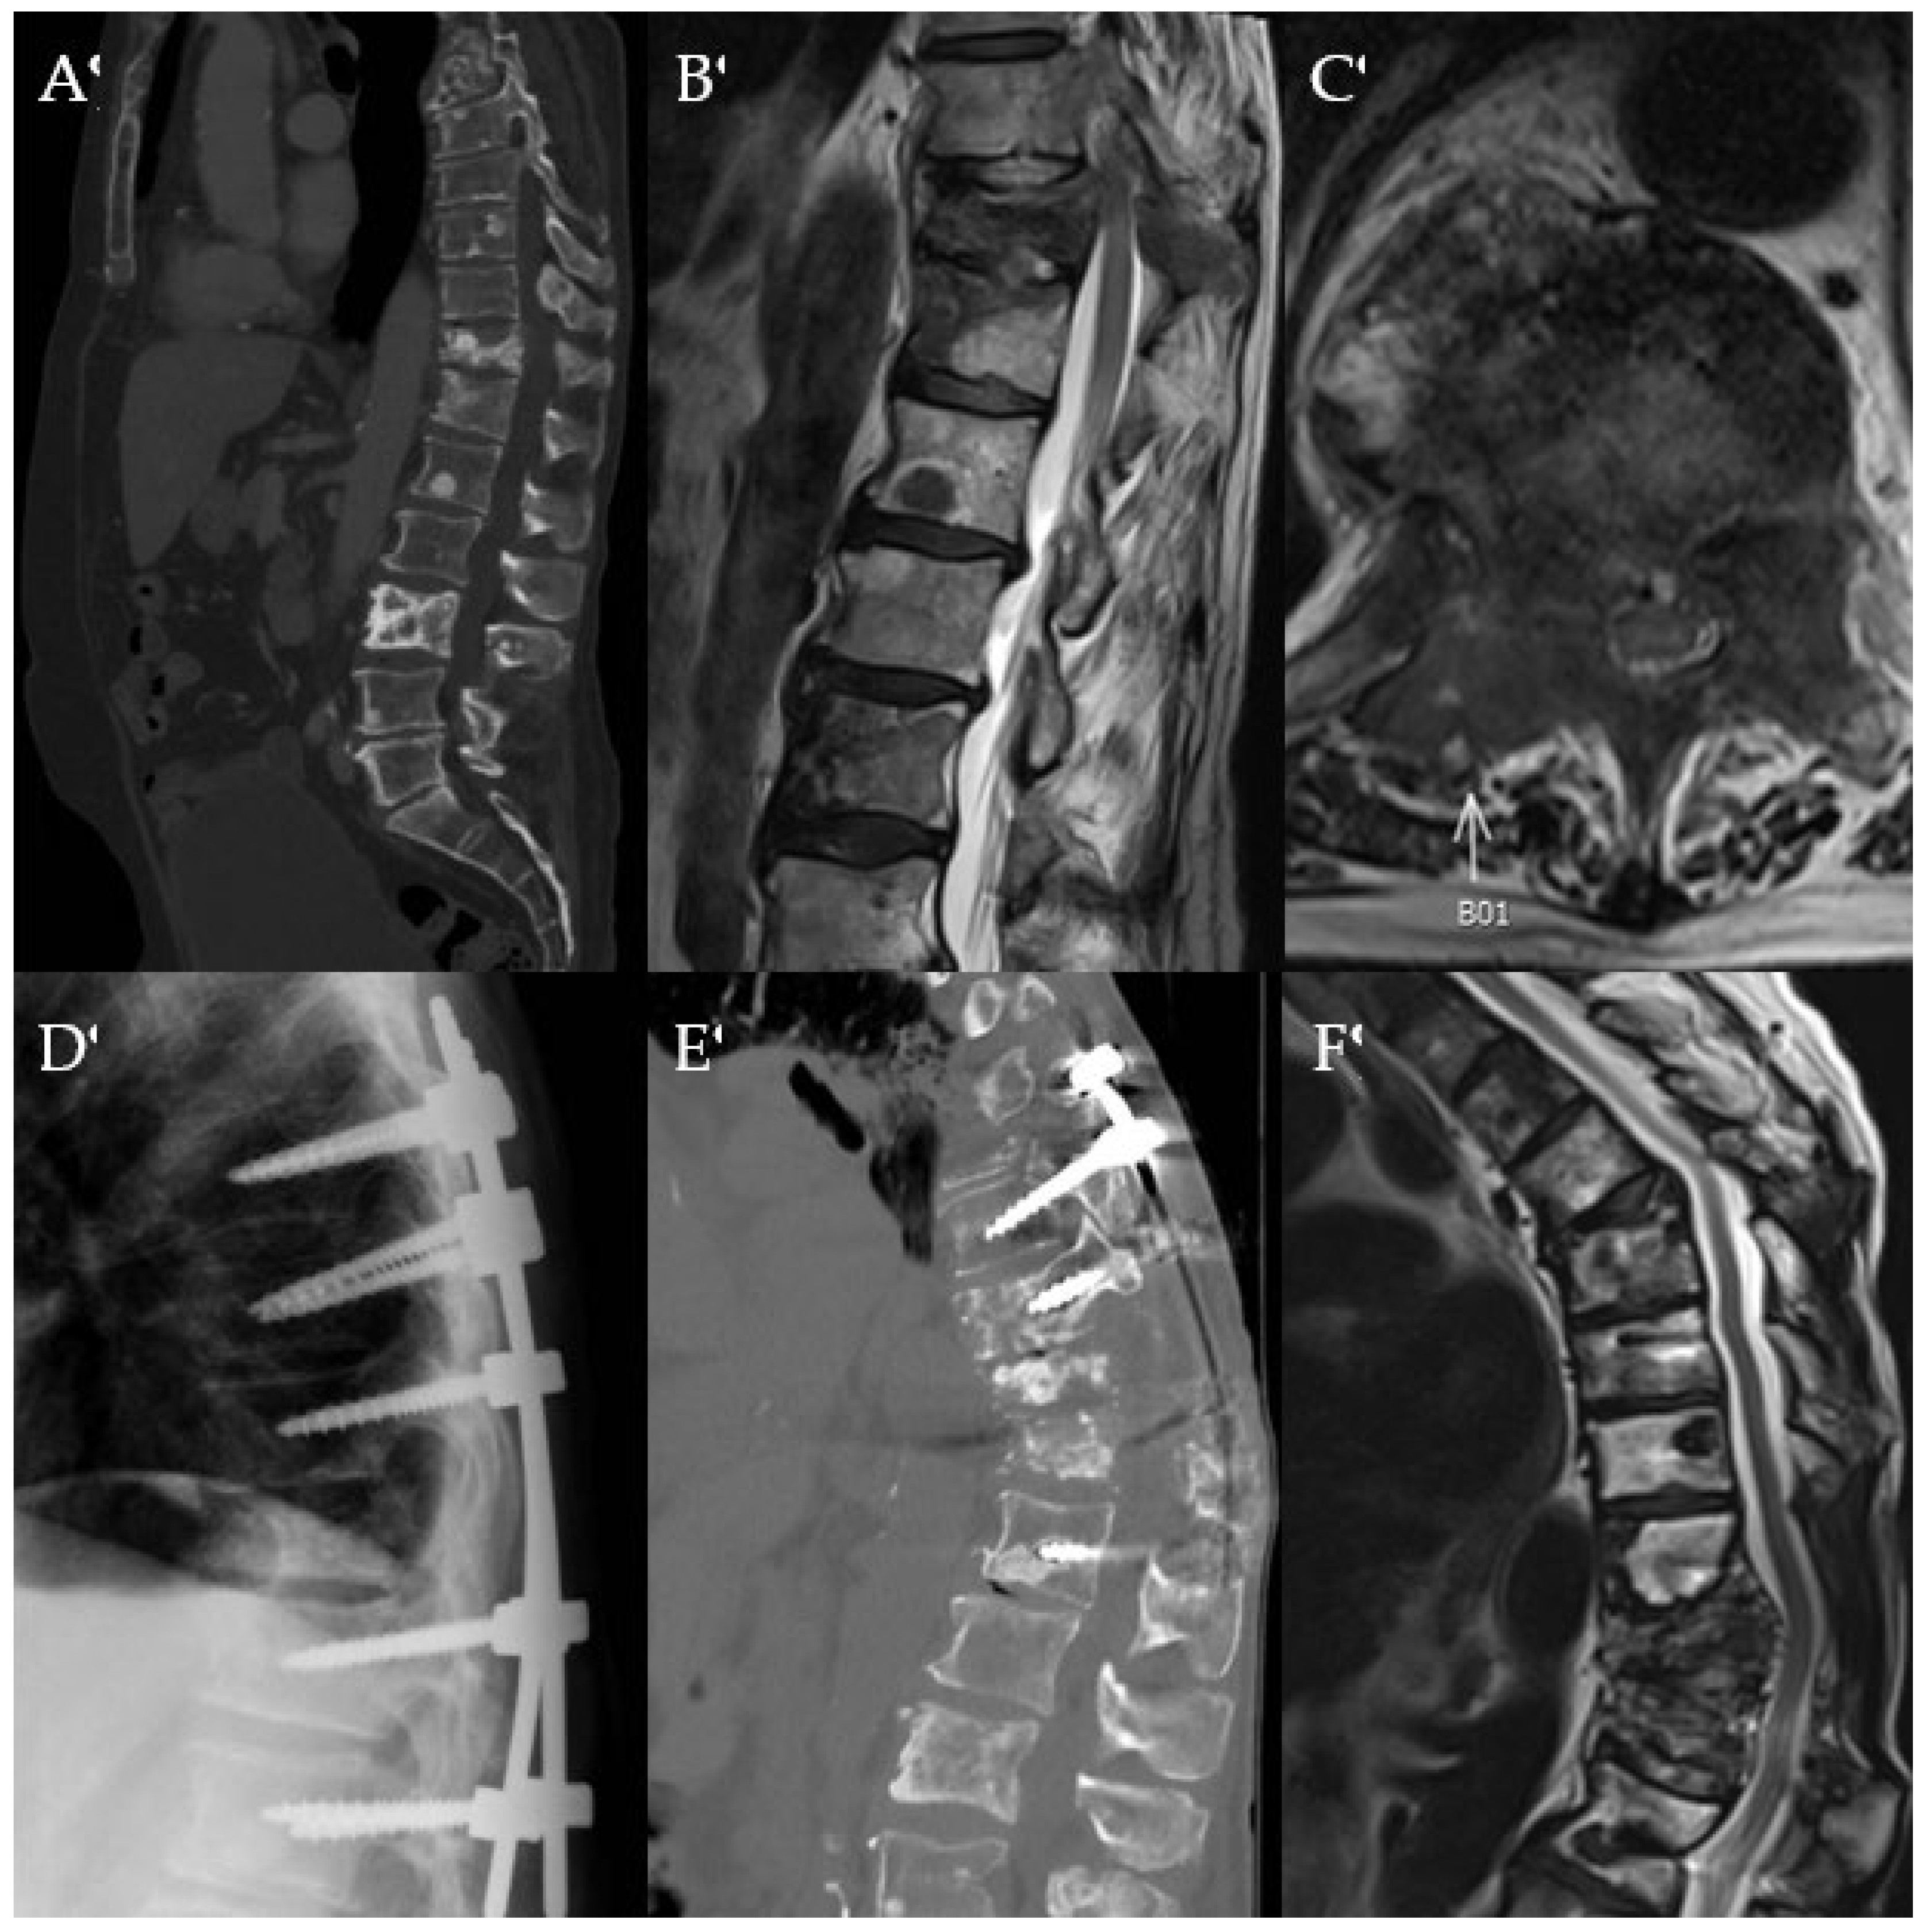

Figure 7. Images of a 68-year-old female with a history of metastatic RCC. Sagittal CT (A) shows destructive changes of the T5 vertebral body. T1 contrast-enhanced MRI sagittal (B) and axial (C) views of the spine show RCC metastases to T5 with canal compromise and circumferential cord compression. Patient underwent preoperative embolization to reduce intraoperative blood loss, followed by T5 corpectomy and posterior instrumentation from T2 to T5 as demonstrated on the immediate postoperative lateral plain radiograph (D) and the 4-month postoperative CT (E). Two-year follow-up CT (F) shows hardware in place without significant change in kyphosis. The patient survived for nearly 2.5 years after surgery.

Currently, the standard surgical treatment for symptomatic SM with ESCC is separation surgery. While the minimal footprint of separation surgery allows patients to resume systemic therapy earlier, the continued improvement in cancer survivorship means such an approach could predispose a select cohort of patients to redo surgeries and/or recurrent radiation treatments (due to local tumor recurrence). Furthermore, it can also result in significant long-term disability and loss of functional independence from chronic pain symptoms as it doesn’t restore spinal alignment and does not achieve circumferential stabilization, resulting in worsening kyphotic deformity and hardware failure (Figure 1) [9,18,19]. In oligometastatic spinal disease patients with good functional status and favorable long-term prognosis, corpectomy with fusion can allow for maximal tumor debulking for improved local disease control, restoration of spinal alignment, and spinal stabilization for long-term pain relief, functional independence, and improved disease-free survival (Figure 7). This study examines corpectomy in selected SM patients for decompression of neural elements and spinal column reconstruction while focusing on the safety, efficacy, and outcomes.

A goal of this study was to determine if corpectomy improved spinal alignment and instability in the immediate and long term. This study revealed that corpectomy for SM significantly improves spinal kyphotic deformity in all spinal segments and allows for long-term correction as measured by Cobb angle (Figure 7). While there is literature in deformity spine surgery that supports the use of corpectomy for improving spinal kyphotic deformity, this study serves to further corroborate that these previously reported findings also apply to SM patients [50,51].